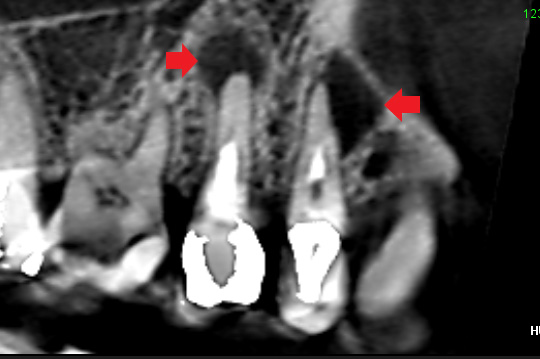

赤い矢印の先に膿の影が認められます。石灰化によって根管が塞がっていたため、根管の途中までしか根管充填できなかったことが考えられます。しかし、石灰化で根管が塞がっているように見えても細菌は侵入していきます。

精密再根管治療の6ヶ月後のCT画像です。2本とも根の先にあった膿の消失を認めることができました。